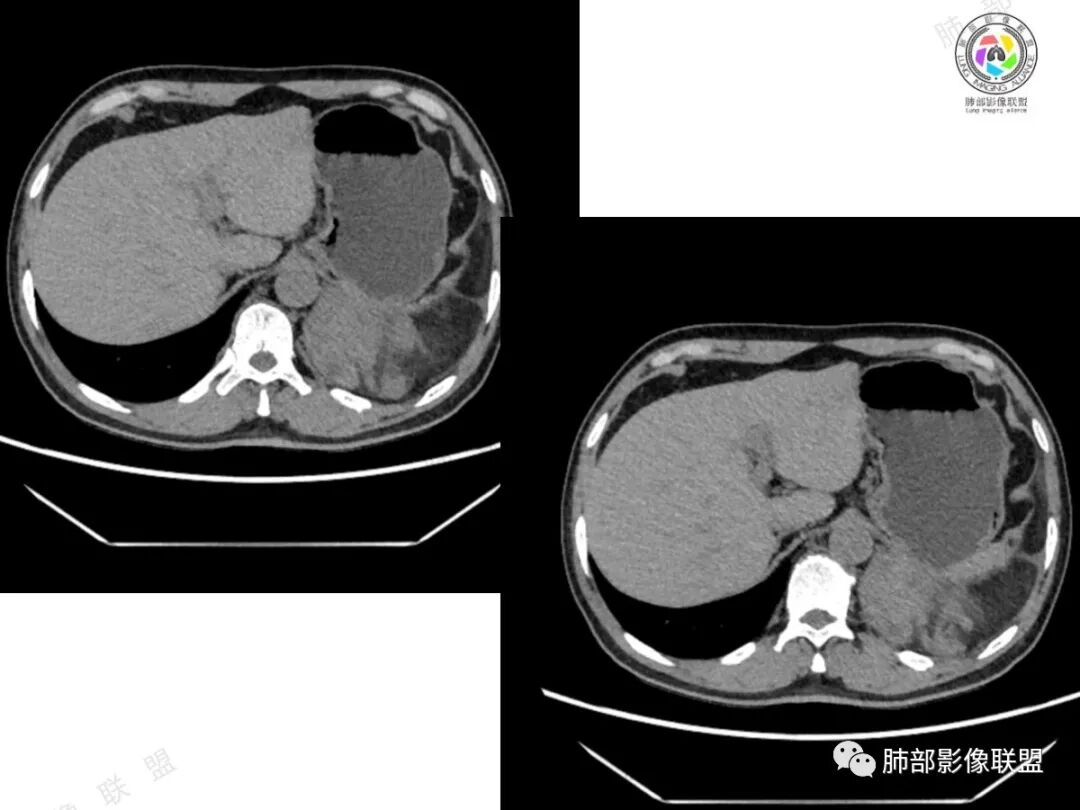

2、影像所见:左侧纵隔紧贴心包铸型生长巨大混杂密度肿块,边界清楚,临近结构受推挤移位,无明显外侵征象。肿块自主动脉弓旁一直顺延到至膈顶,呈“垂乳征”。病灶脂肪成分居多,斑片状、结节状及团块状实性密度成分散落其中,呈地图样分布,实性成分偶见低密度线样分隔,未见明确钙化影。增强扫描实性成分呈延迟明显强化,并见强化血管影。纵隔内有肿大淋巴结,未见胸腔积液,肺内及胸膜未见转移性病灶。

②胸腺脂肪瘤:好发于前下纵隔心膈角区,肿块一般较大,多见于40岁以下年龄患者,其内可见条状或片絮状胸腺组织,一般无周围侵犯。本例实性成分多、体积大,年龄较大,与胸腺脂肪瘤存在较多冲突。

4、疑惑:本例临床病史与影像表现,似乎单纯用一元论不足以解释全部,故要考虑到有无二元共存的可能性。